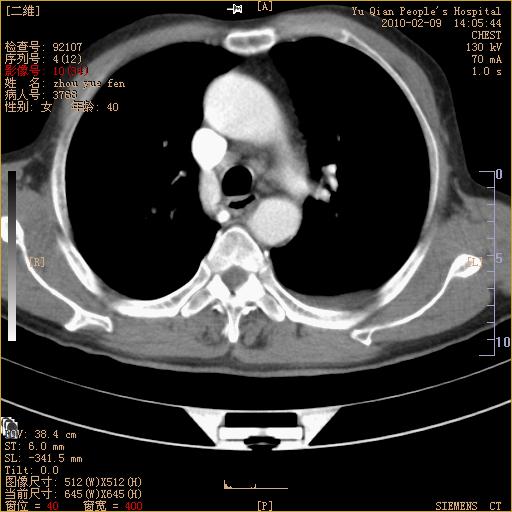

男性,73岁,咳嗽咳血数天,诊为肺ca伴左肺下叶后段阻塞性炎症、肺不张妥否?

右下肺有转移?

左下肺中央型肺癌伴结段形肺不张,左侧胸腔积液,纵隔内见部分增大淋巴结(反应性增生或转移)

左下基底干支气管明显变窄。

左肺下叶基底段支气管狭窄,左肺门增大,左肺下叶团片状病灶。中心型肺癌伴柱塞性炎症可能大,建议支气管镜检查。

左下肺中央型肺癌伴节段性肺不张,左侧胸腔积液,纵隔内见肿大淋巴结

左下基底段支气管变窄。建议进一步纤支镜检查。

1、左肺下叶后基地段肺癌伴阻塞性炎症,左下肺门淋巴结转移。2、左侧胸腔积液。